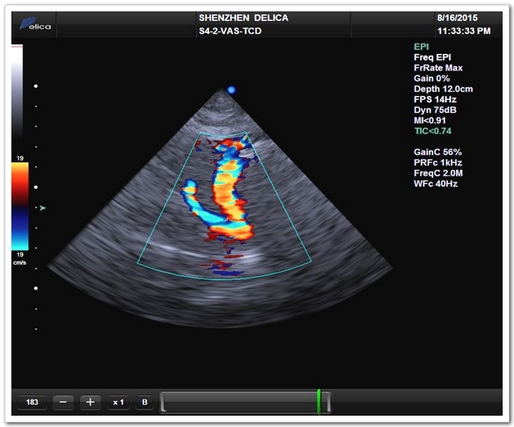

TCD模式(颈内动脉终末段)

心脏超声与颅内血流同屏同步显示

全球唯一!